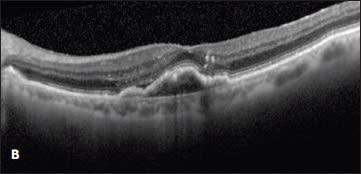

Case 2. The second case involved a 99-year-old woman who presented with a new occult lesion in the left eye. There was loss of one line of vision at 20/40, and a new PED with associated subretinal fluid was noted on her OCT (Figure 2A). She was treated with three doses of monthly bevacizumab with a minimal response, and her vision declined to 20/50+2 (Figure 2B).

She was then switched to monthly ranibizumab. The subretinal fluid resolved with one injection, and her vision improved to 20/30. However, after nine injections of monthly ranibizumab, her vision declined to 20/40, with a small amount of intraretinal fluid and an enlarging PED (Figure 2C). This visit coincided with the commercially availability of aflibercept, and the treatment was changed to monthly 2.0 mg aflibercept. After two injections, her vision improved to 20/30, the PED flattened, and the subretinal fluid resolved (Figure 2D).

Figure 2. A new occult CNV with PED (A). After treatment with bevacizumab, OCT showed persistent subretinal fluid (B). The therapy was switched to ranibizumab, and after nine injections, the PED had slightly grown in size, but the subretinal fluid had resolved (C). Due to PED growth, the patient was switched to aflibercept, and after two injections, the subretinal fluid resolved, and the PED flattened (D).